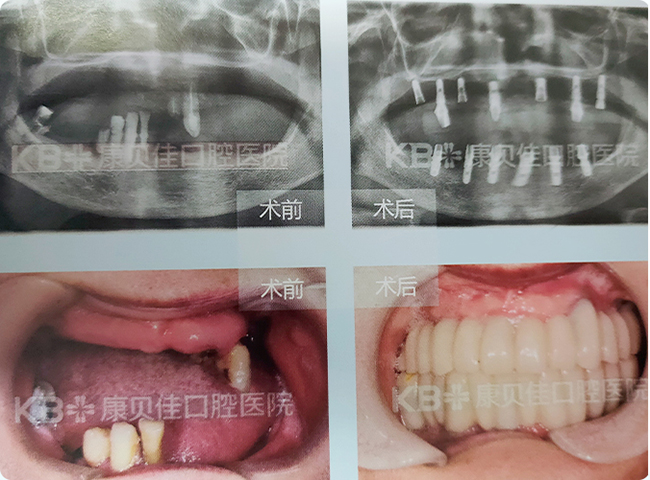

杨女士 57岁

因蛀牙严重在外院做过根管治疗后没有及时戴上保护冠,后因咬硬东西导致上颌4颗牙齿先后裂开,无法保留。经过对比后到我院求医,我院医生为她制定了即拔即种方案,利用拔牙创口即刻植入种植体,术后即刻安装基台和牙冠。

治疗方案:

上颌种植4颗